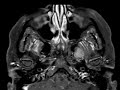

CN V3 Schwannoma

These images show a T1 isointense, T2 Hyperintense, enhancing mass in the left masticator space medial to the left medial pterygoid muscle extending to the skull base with expansion of the foramen ovale. This mass is consistent with a schwannoma of the mandibular division of the trigeminal nerve with extension to the masticator nerve. The differential in this case may include secondary perineural spread of a masticator space malignancy. In this patient with neurofibromatosis type II and multiple meningiomas and bilateral schwannomas, the diagnosis is clear.